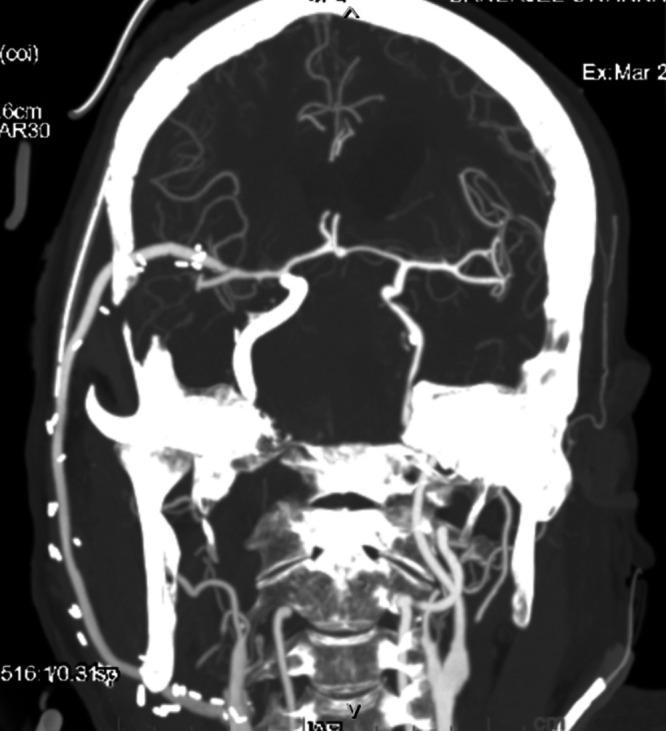

The best treatment option for giant intracranial aneurysms (GIAs) is still debated. The authors report a case of a giant thrombosed cavernous carotid artery (CCA) aneurysm for which two sessions of flow diverter (FD) placement failed, leading to bilateral blindness.

A 66-year-old man presented to an outside center with a history of rapid-onset right-sided retro-orbital pain, visual deterioration, and restricted eye movements associated with headache, vomiting, and diminished sensations on the right side of the face. He was diagnosed with an unruptured thrombosed giant CCA aneurysm and was treated twice with unsuccessful FDs. At follow-up, he developed blindness in both eyes. After 1.5 years, he presented to the authors' institution with headache, vomiting, and epistaxis, for which he underwent high-flow external carotid artery-M2 segment of the middle cerebral artery bypass grafting using the radial artery as a conduit and ligation of the internal carotid artery in the neck without any added neurological deficits.

巨大颅内动脉瘤(GIA)的最佳治疗方案仍存在争议。作者报告了一例巨大血栓形成的海绵窦段颈内动脉(CCA)动脉瘤病例,该病例进行了两次血流导向装置(FD)置入均失败,导致双侧失明。

一名66岁男性因快速发作的右侧眶后疼痛、视力恶化、眼球运动受限伴头痛、呕吐及右侧面部感觉减退的病史就诊于外院。他被诊断为未破裂的血栓形成的巨大CCA动脉瘤,并接受了两次FD治疗,但均未成功。随访时,他出现了双眼失明。1.5年后,他因头痛、呕吐和鼻出血就诊于作者所在机构,为此他接受了以桡动脉为血管桥的高流量颈外动脉-大脑中动脉M2段搭桥术,并结扎了颈部的颈内动脉,术后未出现任何新增神经功能缺损。